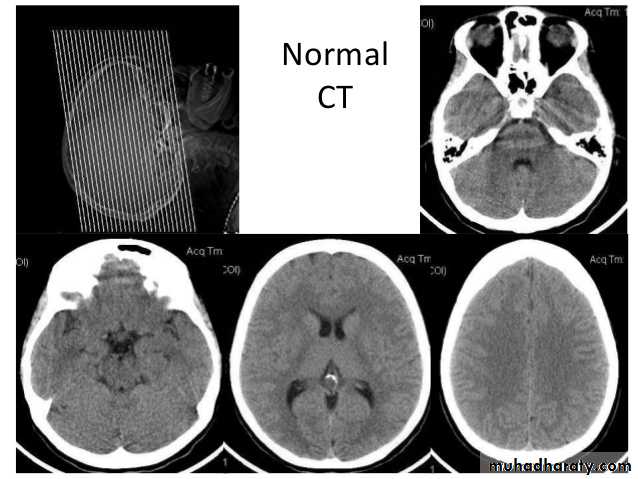

Common CT findings of traumatic brain injury